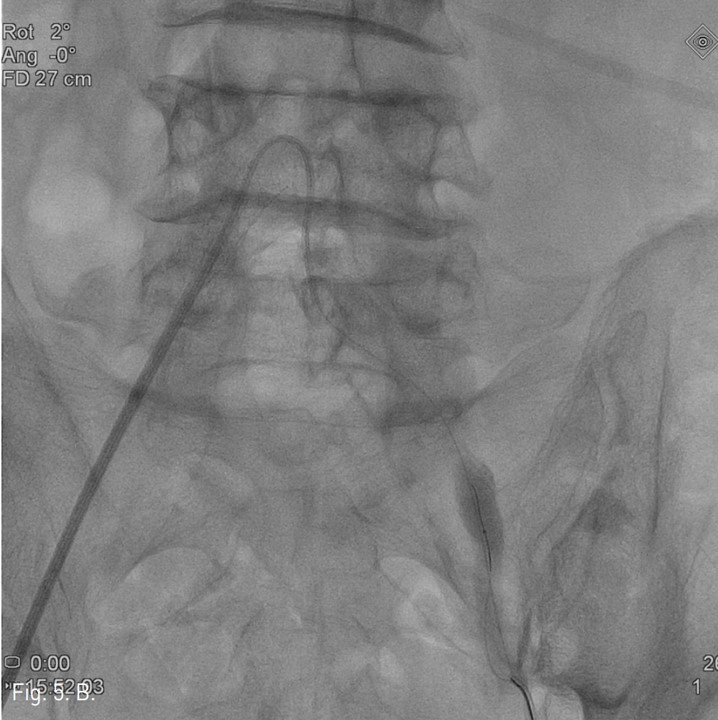

컴퓨터단층촬영 혈관조 영술과 고식적 혈관조영술에서 우측 총장골동맥에 석회화를 동반한 80%정도의 심한 협착이 있고, 좌측 총장골동맥에서 외장골동맥에 석회화를 동반한 완전 폐쇄의 소견이 있다 (Fig. 1A, IB). 우총대퇴동맥의 근위부에 10mm x 29mm Zenesis stent를 설치하였다 (Fig. 2). 0.035 inch guidewire로 좌측 총장골동맥의 기시부 폐쇄부위 통과를 시도하였으나 가성내강에서 진성내강으로 재진입이 되지 않았다 (Fig. 3). 좌측 외장골동맥 진성내강 내에 있는 ‘L-자’ 표시방향의 outback device가 보인다 (Fig. 4A), 좌측 외장골동맥 진성내강 내에 있는 'T-자’ 표시방향의 outback device가 보인다(Fig. 4B). Outback device를 이용하여 동맥내막을 천자후 0.014 inch guidewire를 가성내강 내로 진입시켰지만 좌측 총장골동맥-외장골동맥경 계부위에서 더 이상 진행되지 않았다 (Fig. 4C). 0.014 inch guidewire를 따라서 Davis catheter를 가성내강 내로 진입시키고 (Fig. 5A), 10mm snare를 삽입하여 Simmon catheter내부에 있던 microwire를 전진시켜 snare로 잡아 좌측 sheath로 뽑아내어 (Fig. 5B), 5Fr. Davis catheter를 대동맥 내부로 진입시켰다(Fig. 5C). 양측 총장골동맥 및 좌측 외장골동맥 스텐트 설치후 대동맥장골동맥조영술상에서 양측 장골동맥의 완전한 재개통을 보인다 (Fig. 6).

Fig. 5. A

Fig. 5. A and 5B. Radiograph obtained at the moment of capturing proximal microwire using a snare.

Fig. 5. B